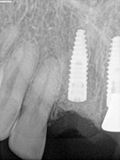

fredlibc | all galleries >> Galleries >> RYang - 11 + immediate 21 and 22 > R6.jpg

R6.jpg